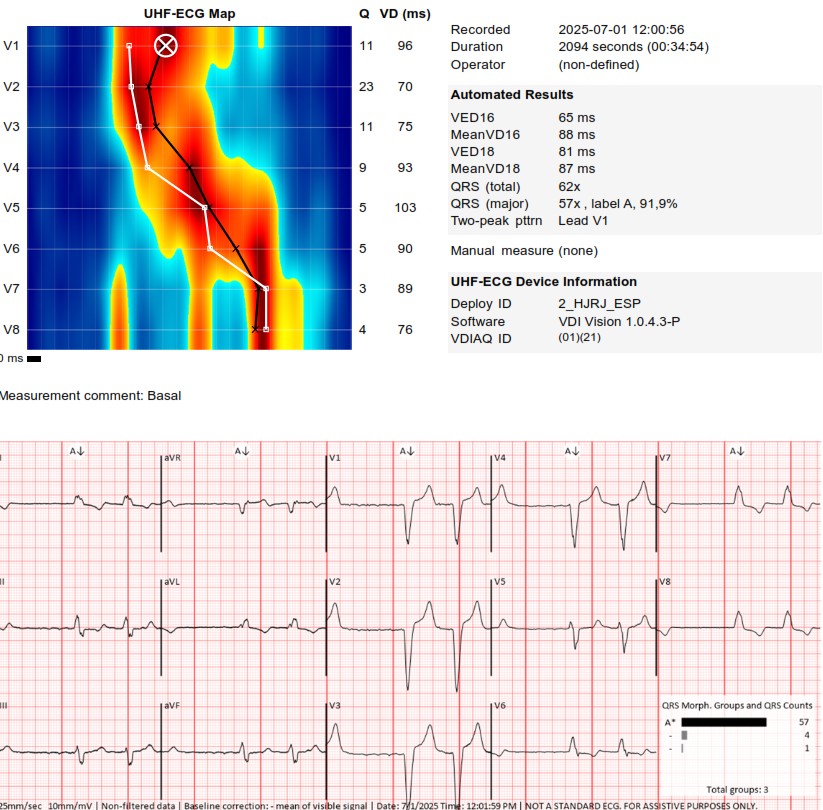

I strongly support HBP, but in this case,the great improvement in QRS didn't correct the asynchrony measured with UHF ECG.We opted for LBBAP despite the RV delay.The final programming AV 70 ms and fusion with native rhythm achieved the best result with UHF ECG(very useful tool)

An interesting case was shared today. UHF-ECG can help to enhance the decision-making in less textbook-type cases.

These are UHF maps of the two patterns. The second one is a little bit deeper into the septum,